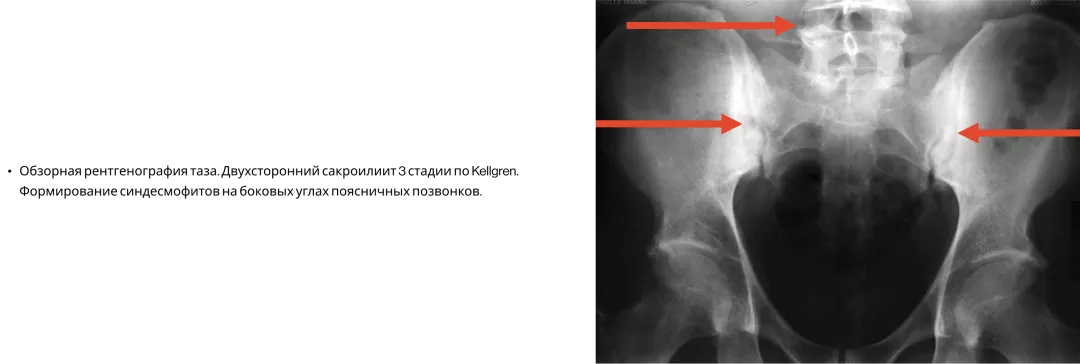

Сакроилиит при ПсА3

Сакроилиит при рентгенографии диагностируется примерно у 30% больных ПсА, при этом каждый четвертый (26%) пациент не жаловался на боль в спине. Поэтому наличие аксиальных поражений при ПсА необходимо активно выявлять3.

Image

Frame 24062083 (1).png

У пациентов с ПсА молчащий сакроилиит. Нужно активно выявлять ВБС!3,18

Frame 24062084 (1).png